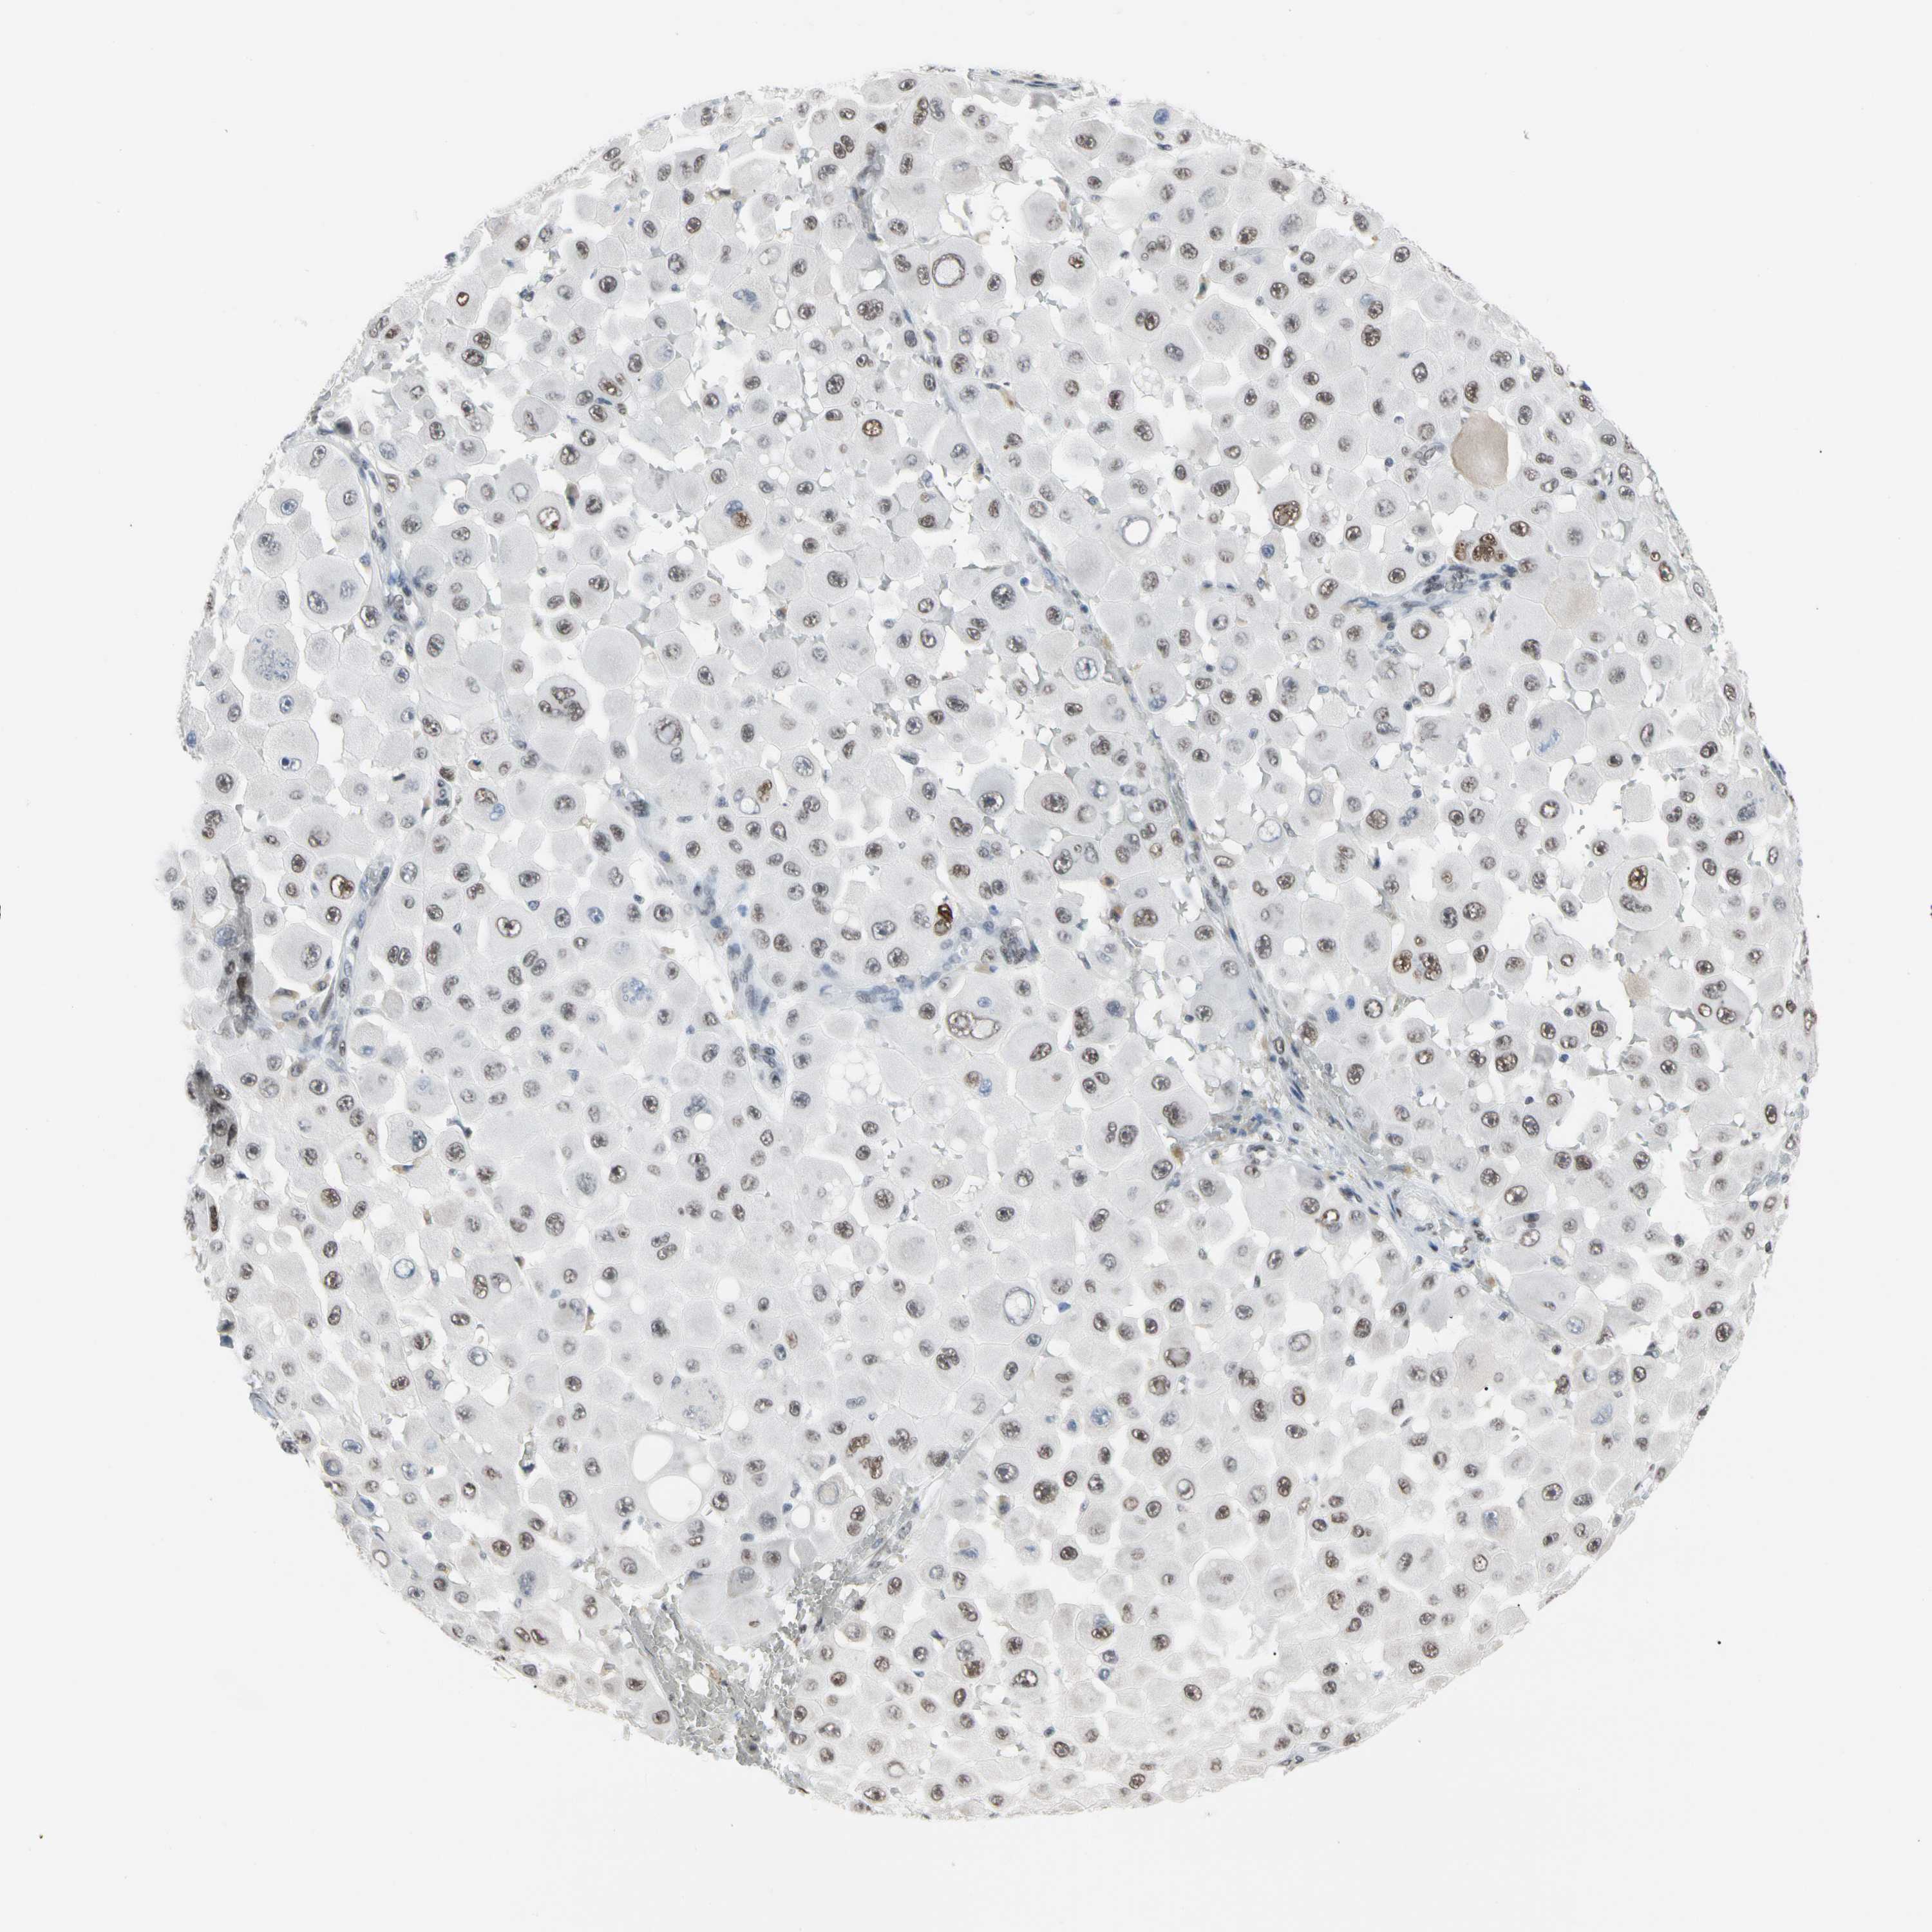

MELANOMA - Protein expressioni

A mouse-over function shows sample information and annotation data. Click on an image to view it in a full screen mode. Samples can be filtered based on level of antibody staining by selecting one or several of the following categories: high, medium, low and not detected. The assay and annotation is described here.

Note that samples used for immunohistochemistry by the Human Protein Atlas do not correspond to samples in the TCGA dataset.

Antibody stainingi

Antibody staining in the annotated cell types in the current human tissue is reported as not detected, low, medium, or high, based on conventional immunohistochemistry profiling in selected tissues. This score is based on the combination of the staining intensity and fraction of stained cells.

Each image is clickable and will lead to virtual microscopy that enables deeper exploration of all samples and also displays staining intensity scores, fraction scores and subcellular localization as well as patient and tissue information for each sample.

Antibody HPA008320

Antibody HPA008502

Staining

High

Medium

Low

Not detected

Intensity

Strong

Moderate

Weak

Negative

Quantity

>75%

75%-25%

<25%

None

Location

Nuclear

Cytoplasmic/membranous

Cytoplasmic/membranous,nuclear

Malignant melanoma, NOS

Malignant melanoma, Metastatic site